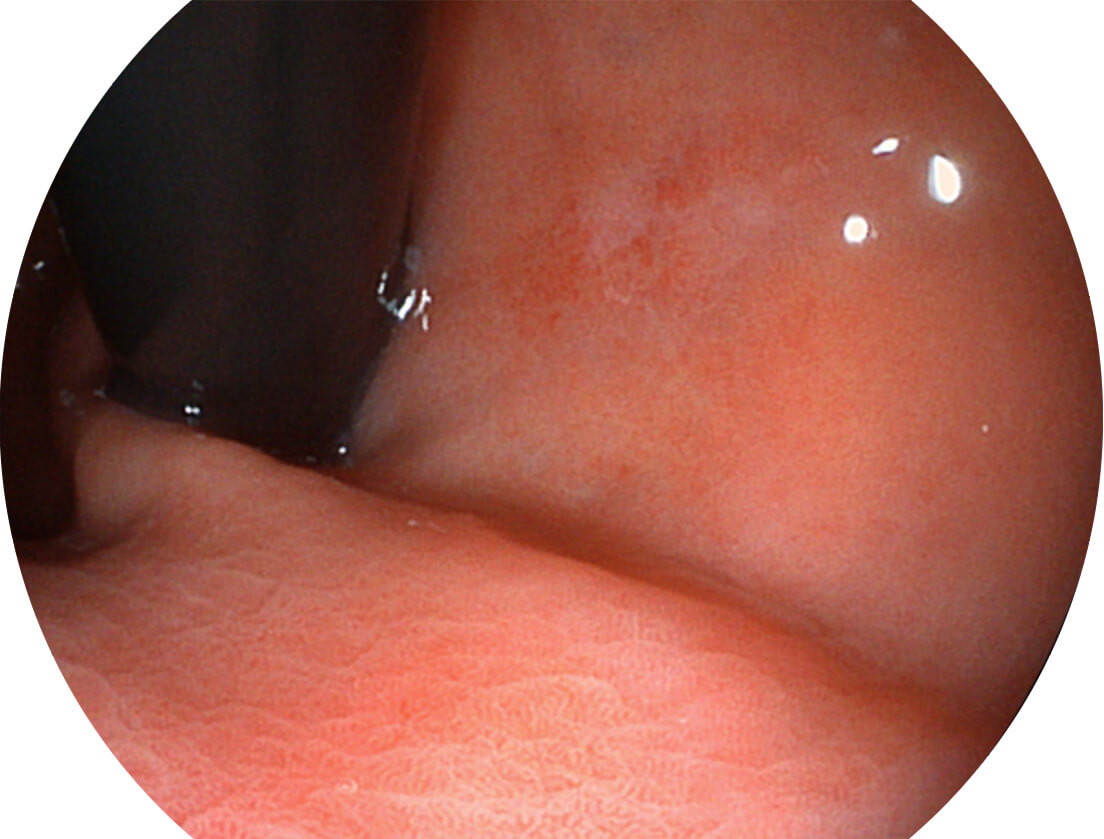

SFI图像

白光图像